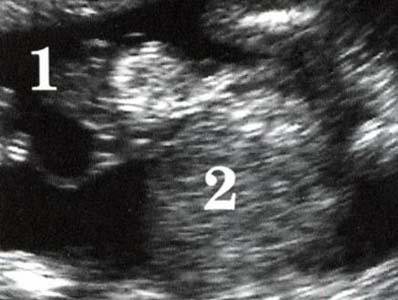

Profil harmonieux